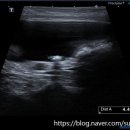

• 선부중앙동물의료센터 | 안산 고양이 이물 수술 전문 | 선부중앙동물의료센터 소화기 수술 후기 및 입원 관리

안녕하세요, 안산의 모든 반려가족분들! 선부중앙동물의료센터입니다. 🐾 고양이를 키우는 집사님들이라면 한 번쯤 '혹시 우리 아이가 이걸 먹은 건 아닐까?' 하는 걱정에 가슴이 철렁했던 적 있으실 거예요. 고양이는 호기심이 많고 혀의 돌기 때문에 이물질을 삼키기 쉬운 구조를 가지고 있거든요. 오늘은 소화기 이물...

안산 반려동물 건강의 중심, 선부중앙동물의료센터(2026-04-24 14:45:00)